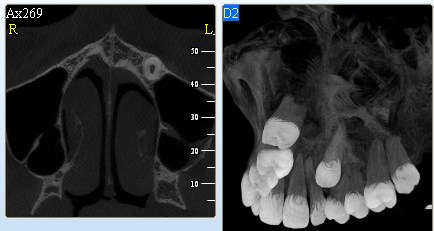

3D DVT - NewTom

Je speciální zubní digitální tříprostorový tomograf (3D), který umožňuje na základě jediného snímkování vytvořit všechny typy RTG zobrazení, které jsou pro lékaře potřebné. Díky používané technologii tzv. „kuželového paprsku“ a speciálním senzorům je výrazně zmenšená dávka záření - o více jak 80% proti klasickému CT vyšetření. To je významné zejména u dětí. Pomocí tohoto přístroje je možné zjisti skutečnou situaci v čelistních kostech pacienta tedy množství kosti - můžeme změřit skutečnou šířku i výšku kosti, i kvalitu kosti (hustotu) v místě uvažované implantace. 3D (tříprostorové) zobrazení umožňuje zvýšit prostorovou představu operatéra ještě před vlastní operací a zároveň pacientovi lépe objasnit a ukázat oblast plánovaného zavedení implantátu.

Vyšetření pomocí tohoto přístroje používáme i ve stomatochirurgii (zlomeniny čelistí, zuby moudrosti, cysty, onemocnění čelistního kloubu), ortodoncii (retinované zuby, nadpočetné zuby), parodontologii atd.

Jedná se o nejnovějším přístroj ze skupiny dentálních hybridních CBCT (3D) + 2D (pan i ceph) systémů. Opět umožňuje na základě jediného snímkování vytvořit všechny typy RTG zobrazení, které jsou pro lékaře potřebné. Používaná technologii tzv. „kuželového paprsku“ a speciální senzory pro minimální zátěž při snímkování pacienta.

Vyšetření pomocí tohoto přístroje (nebo 3D DVT - NewTom) a získaná data používáme pro každou implantaci, dále ve stomatochirurgii (zlomeniny čelistí, zuby moudrosti, cysty, onemocnění čelistního kloubu), ortodoncii (retinované zuby, nadpočetné zuby), parodontologii atd.